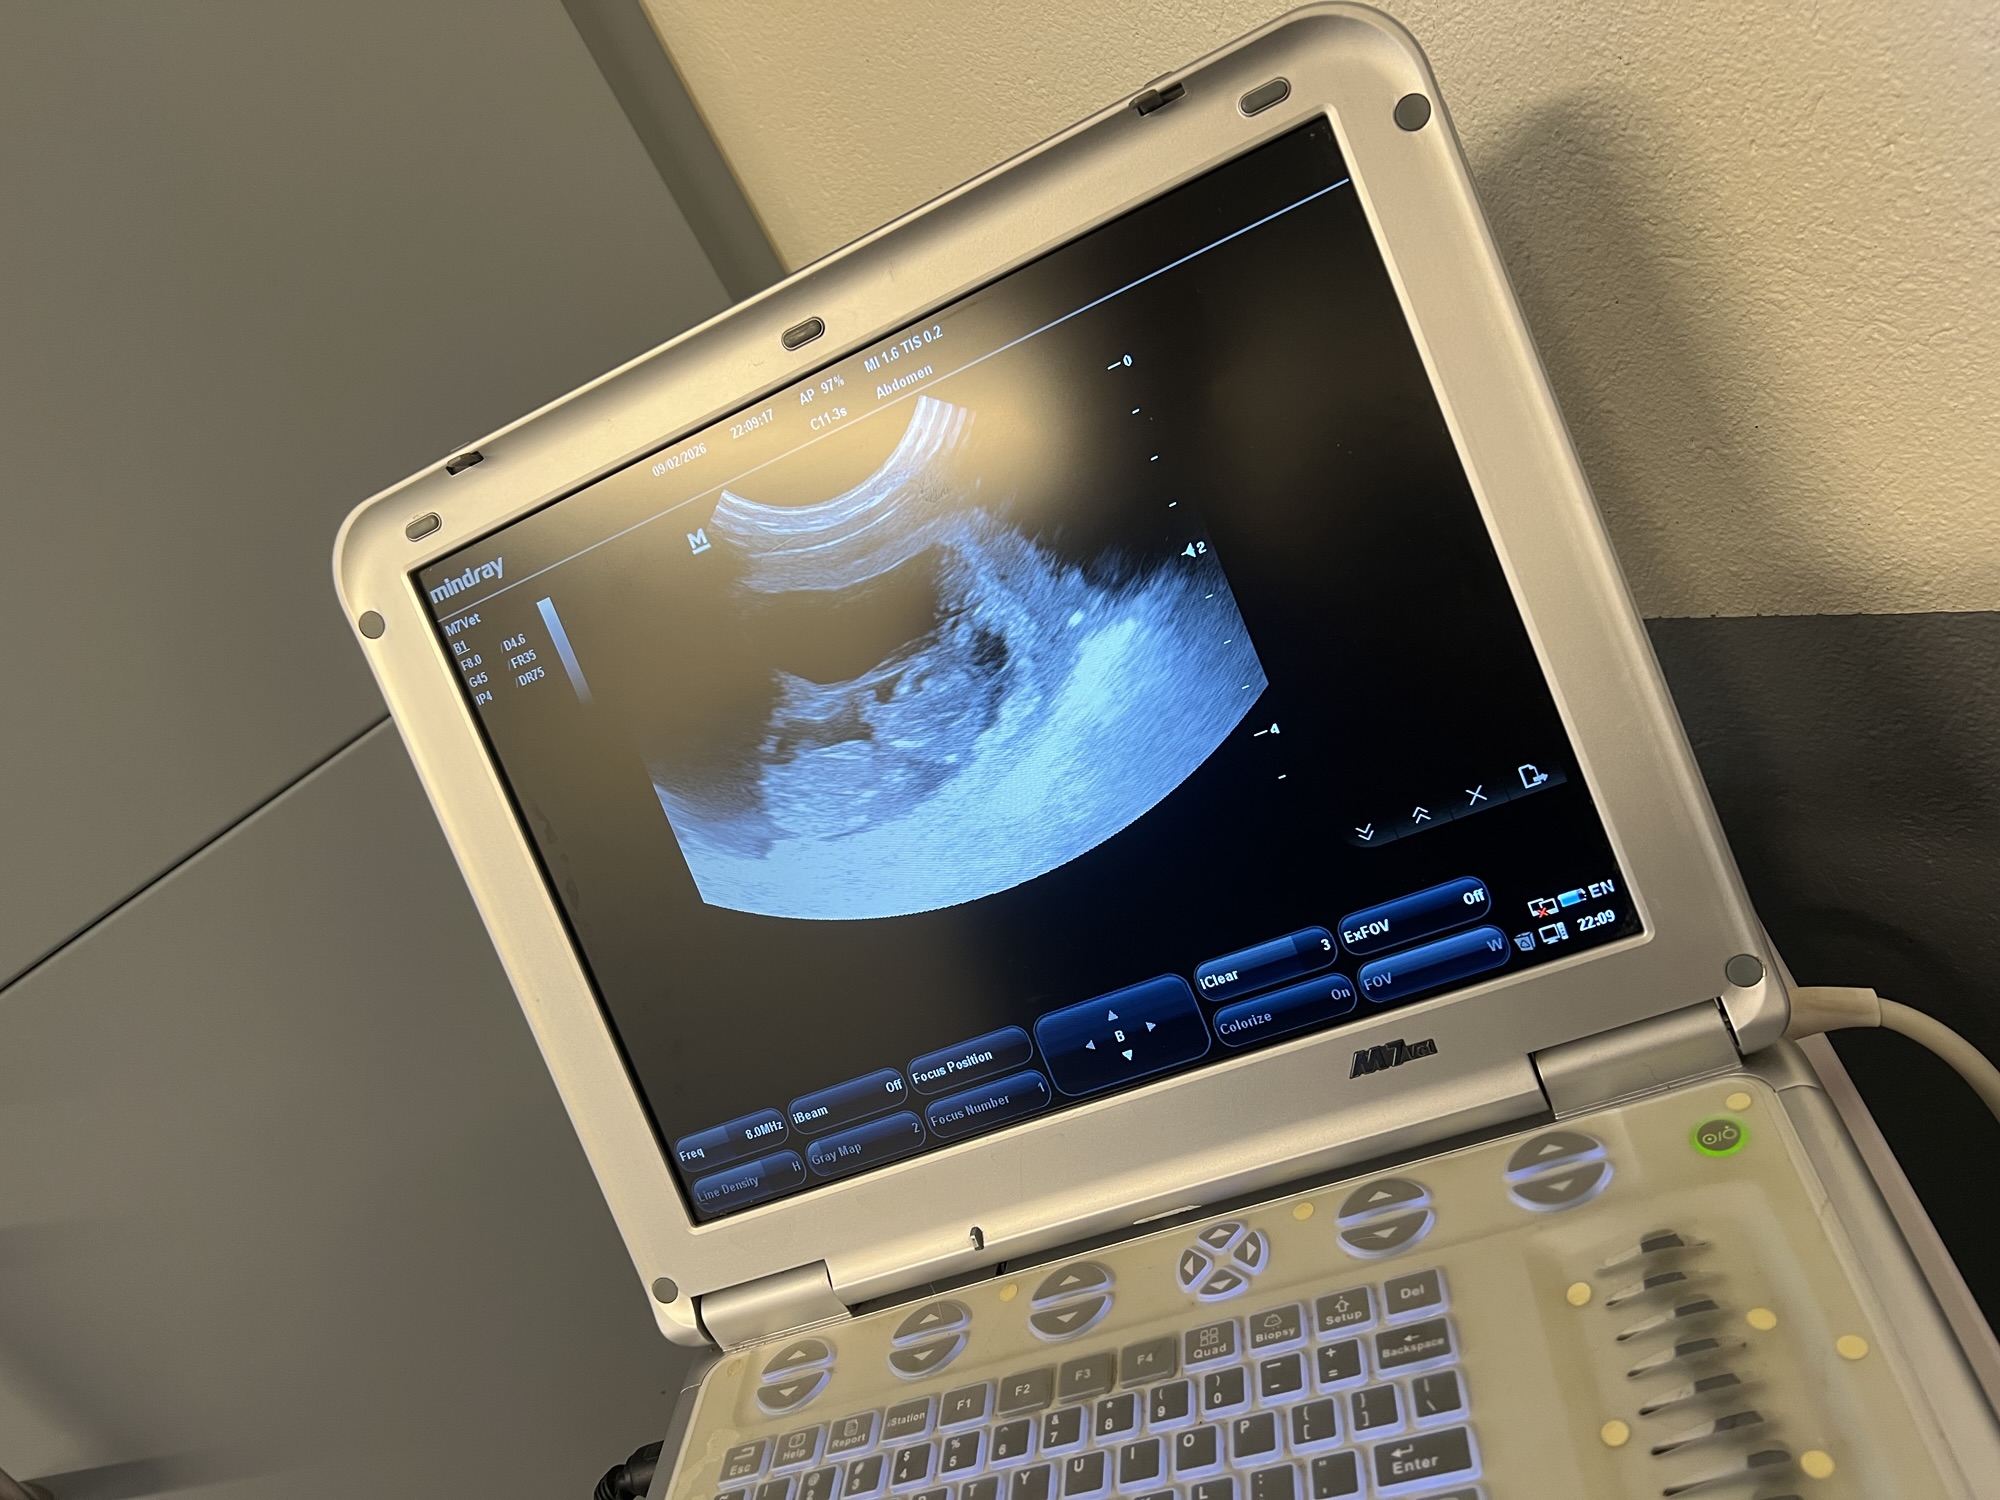

I skånsk snökaos i Januari var vi iväg och parade vår Ixia med fina Flinkagårdens Alfred. Men denna gången gick det inte vår väg, i tisdags när Ixia gått någon dag över tiden var vi nere hos Veterinärerna på Bollerup för att göra ett ultraljud för att se så att valparna mådde bra. Tyvärr så fanns där ingen hjärtaktivitet. Så igår genomgick Ixia ett kjejsarsnitt där man plockade ut två valpar, en tik och en hane, Stor och Liten. Nu är det vår prioritet att se till att Ixia läker och återhämtar sig. Dock så är vi så ledsna för de två familjerna som såg framemot att få välkomna varsin valp till sommaren. Vi vill än en gång rikta ett stort tack till personalen på Veterinärerna på Bollerup för otroligt fint bemötande och omhändertagande. Det är så viktigt att vi ser till att vårda våra lokala veterinärer och att vi värdesätter att de finns där för oss när vi behöver dom. Nu ska vi försöka ta in vad vi har varit med om och se framemot en fin sommar och sen får vi se vad tiden har framömför oss! Ta han om er och krama era hundar lite extra. 20260319